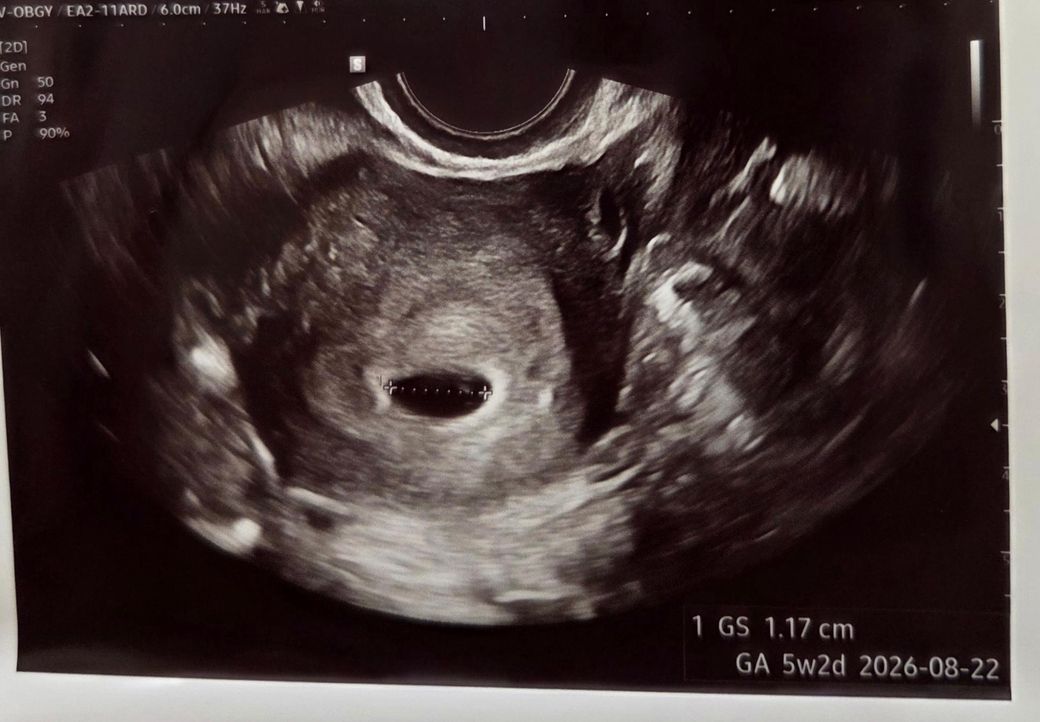

주수로는 4주5일차인데 선생님께서 아기집에 비해 난황이 점 찍어놓은것 같이 너무 작다고, 염려가 된다하셨어요ㅠㅠ6개월전에 화유 1회경험이 있어서 너무 불안해요...1주일 뒤에 다시 초음파 보자고 하는데 제 상황이 많이 안좋은걸까요?

선생님이 무수히 많은 아기집을 봤지만 아기집 크기에 비해 난황이 너무 작다고 완전히 정상이라고 말할수가 없대요...너무 불안합니다.

• 1번 째 사진